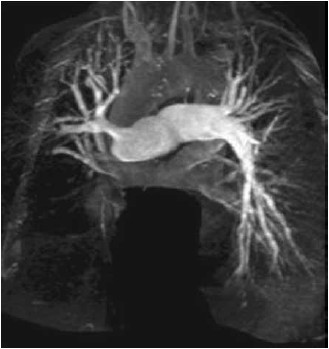

Mulher de 32 anos apresenta dispneia progressiva aos esforços no último ano. O exame físico é notável para: pressão arterial: 123 x 81 mmHg; frequência cardíaca: 91/min, saturação de oxigênio: 91%; pulmões limpos; ausculta cardíaca com componente pulmonar alto de B2; edema simétrico de membros inferiores. Há 4 meses ela usa furosemida, enalapril e apixabana, com pouca melhora clínica. O cateterismo cardíaco direito mostra: pressão atrial direita: 14 mmHg; pressão arterial pulmonar (média): 38 mmHg; resistência vascular pulmonar: 6,8 unidades Wood (544 dinas por segundo por cm-5); pressão capilar pulmonar: 8 mmHg. A angiografia pulmonar é mostrada a seguir.

(Arquivo pessoal: imagem usada com autorização.)

Nessa paciente, a conduta mais apropriada é